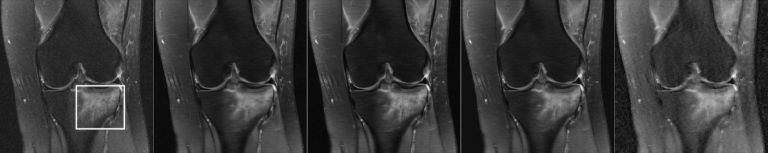

We are happy to announce that our manuscript "How AI May Transform Musculoskeletal Imaging" (https://pubs.rsna.org/doi/10.1148/radiol.230764) just got published in Radiology. This was a joint effort with colleagues from Boston University, University of Lausanne, University Paris Cité, NYU, Clinique ...